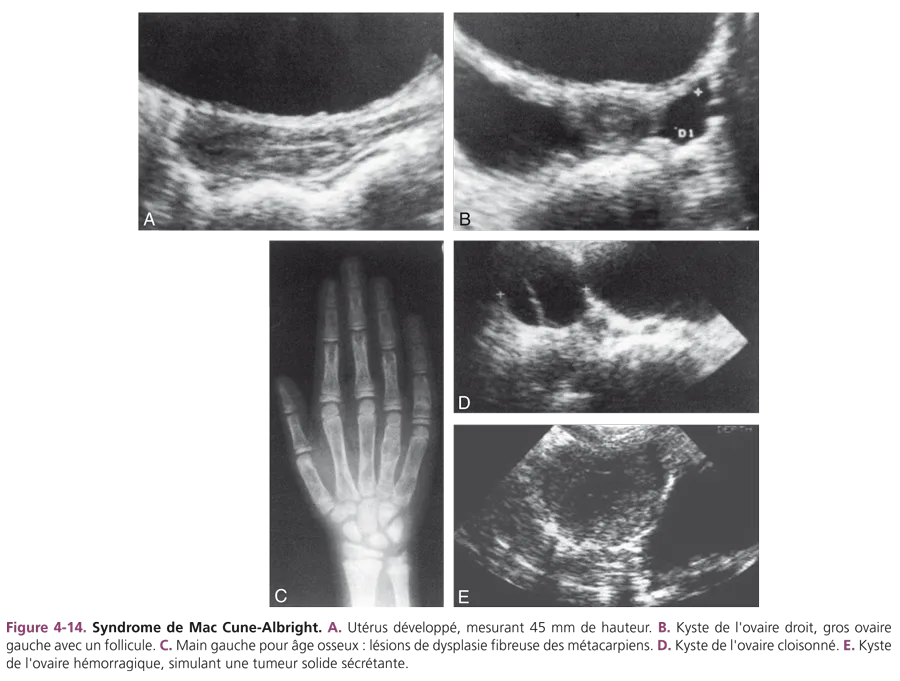

Syndrome de Mac Cune-Albright [7] Il associe typiquement une précocité pubertaire dissociée d’origine ovarienne, des taches pigmentaires cutanées et une dysplasie fibreuse des os. Le taux d’œstradiol sanguin est souvent très élevé avec un test de stimulation à la GnRH plat, témoin du dysfonctionnement primitif ovarien. L’échographie retrouve un développement évident des organes génitaux internes. Les ovaires bien développés présentent très souvent des kystes uni- ou bilatéraux (fig. 4-14) qui peuvent être ponctionnés s’ils sont douloureux. Ces kystes sont parfois hémorragiques prenant alors une échostructure solide, hétérogène et leur découverte initiale peut simuler alors une tumeur sécrétante de l’ovaire. Un contrôle échographique à distance permet de rectifier le diagnostic en visualisant les modifications du contenu du kyste.

Des radiographies du squelette complet recherchent des lésions de dysplasie fibreuse des os. Le syndrome de Mac Cune-Albright est lié à une pathologie des récepteurs membranaires (anomalie de la protéine G), qui entraîne un syndrome d’autonomisation polyorganique. D’autres endocrinopathies (atteinte thyroïdienne, atteinte surrénalienne et hypophysaire) peuvent s’associer.